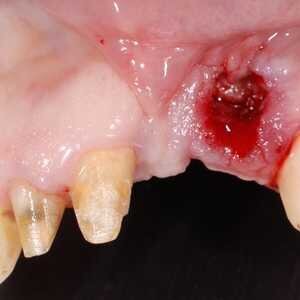

Dans cet article, nous présentons un cas clinique qui montre comment une mauvaise mise en place d'un implant peut rendre impossible la réhabilitation prothétique, ce qui nécessite une nouvelle planification chirurgicale et de réhabilitation pour obtenir l'esthétique souhaitée. Le patient se présente à notre observation avec une réhabilitation prothétique incongrue, avec bride en résine, support dentaire et implantaire, avec la présence d'un implant en position 2.1 vestibulaire et avec l'émergence dans le fornix, dans la mucosa alvéolaire. L'évaluation de la tomodensitométrie montre la position incorrecte de l'implant et la perte constante dans le sens transversal de la structure osseuse (Figs. 1, 2). Par conséquent, le plan de traitement suivant a été choisi : retrait de l'implant et préparation prothétique de l'élément 2.3, fabrication d'un premier support dentaire temporaire pour guider la cicatrisation des tissus (Figs. 3-7). Après 4 mois, une greffe d'épithélium conjonctif libre est réalisée avec ablation du palais pour compenser l'espace transversal des tissus mous, puis le provisoire est remodelé afin de faciliter la cicatrisation des tissus (Figures 8-11). Après 9 mois de maturation des tissus, la finalisation prothétique fixe avec support dentaire est réalisée (Figs. 12-14).